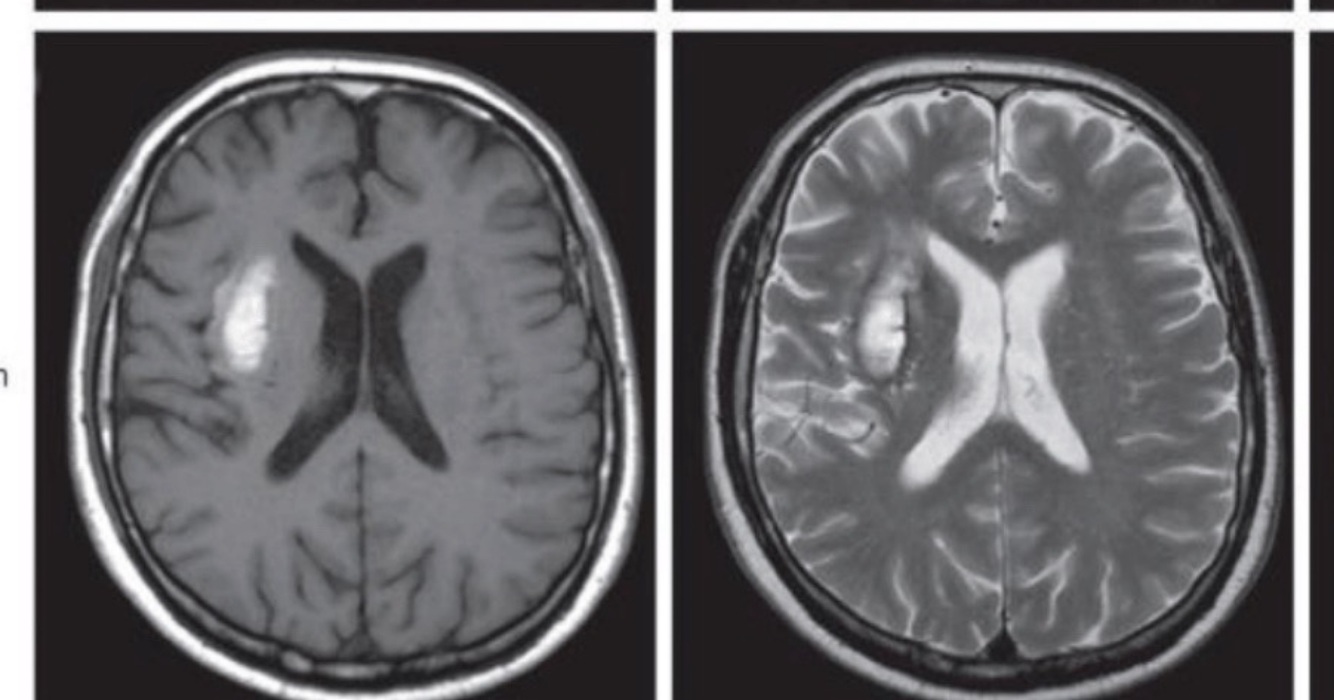

A

EVC isquémico crónico